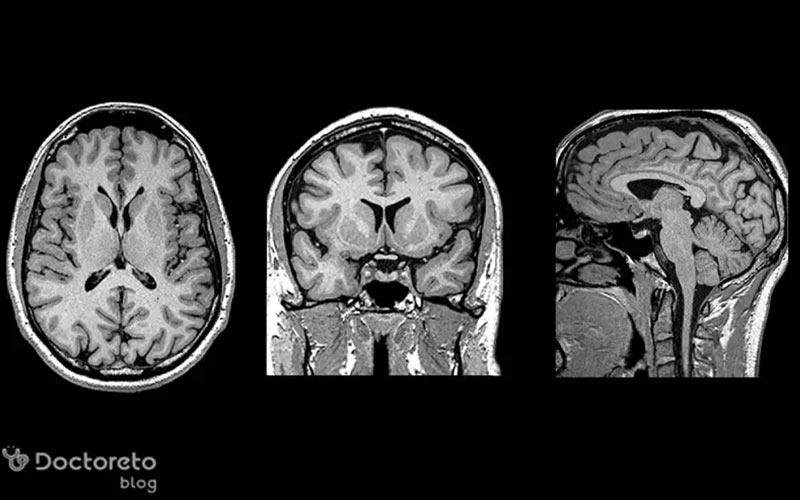

امواج مغزی در نوار مغز تشنج بسته به محلی که فعالیت غیرطبیعی از آن آغاز میشود، تشنج فوکال یا ژنرالیزه است. تشنجهای کانونی یا فوکال ابتدا در یک ناحیه مشخص از مغز شروع شده و ممکن است به مناطق دیگر گسترش یابند. در حالی که تشنجهای ژنرالیزه از ابتدا نواحی وسیعی از هر دو نیمکره را درگیر میکنند. شناخت محل انتشار تشنج در نوار مغز به پزشکان کمک میکند تا نوع تشنج، مسیرهای انتشار و گزینههای درمانی مناسب را تعیین کنند و پیشبینی دقیقی از روند بیماری داشته باشند. برای تشخیص تشنج در نوار مغز و تفسیر آن میتوانید از بهترین دکتر مغز و اعصاب و نورولوژی ایران مشاوره بگیرید.

تشنجهای کانونی یا تشنج فوکال به فعالیت الکتریکی غیر طبیعی محدود به یک ناحیه از یک نیمکره مغزی اشاره دارند. این نوع تشنجها ممکن است در هر ناحیهای از مغز شروع شوند و بسته به محل شروع، علائم بالینی متفاوتی ایجاد کنند؛ مثلاً در تشنجهایی که از لوب تمپورال یا لوب پیشانی منشا میگیرند، اختلالات حسی، حرکتی یا تغییرات شناختی دیده میشود. نوار مغز در این موارد الگوهایی از فعالیت غیر طبیعی را نشان میدهد که تنها در لایههای الکترودهای نزدیک به ناحیه درگیر دیده میشوند و اغلب با موجهای تیز (spikes) یا Sharp wave همراه هستند.

فعالیت الکتریکی کانونی میتواند در طول زمان به نواحی دیگر گسترش یابد و شکل گستردهتری به خود بگیرد؛ به همین دلیل گاهی تشخیص دقیق محل شروع نیازمند تحلیل ویدیویی همزمان با نوار مغز (Video-EEG) است. تشخیص کانون و مسیر انتشار میتواند در تعیین گزینههای درمانی، از جمله دارودرمانی یا جراحی، نقش مهمی داشته باشد.